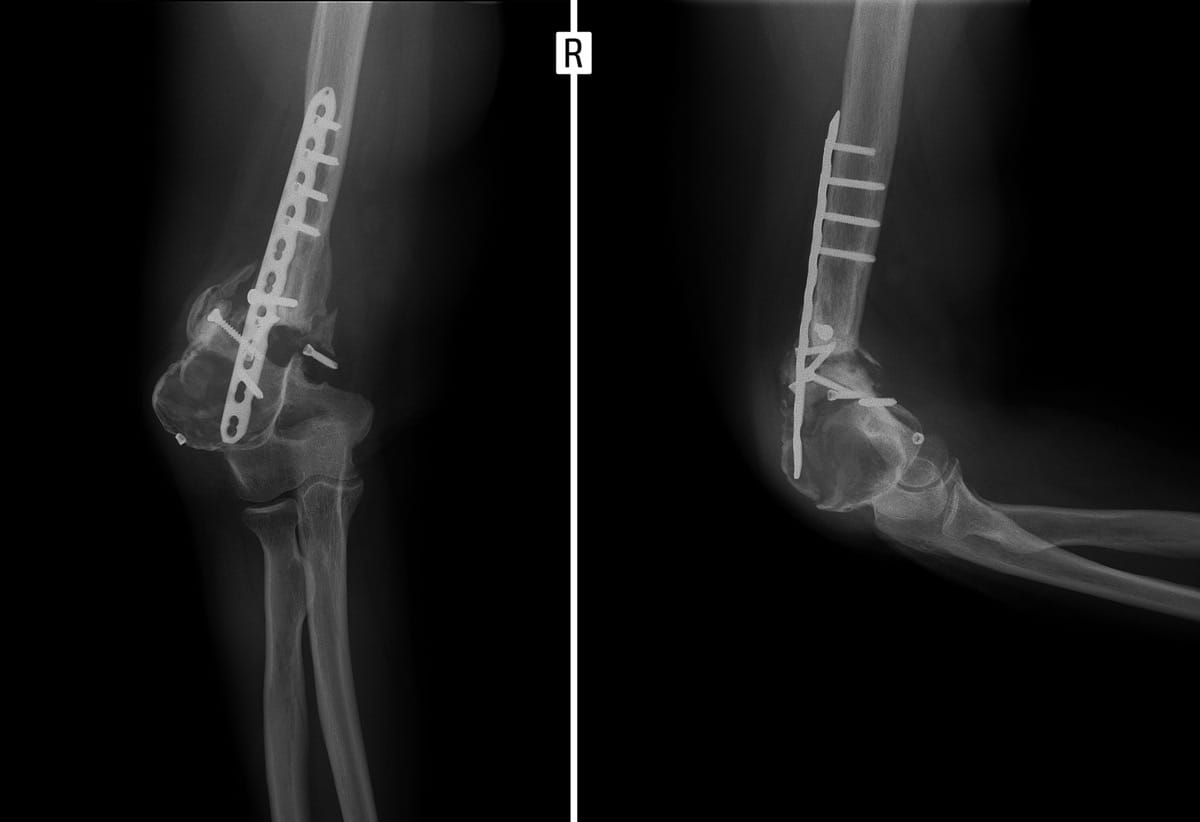

Podstawowym i najczęściej wystarczającym badaniem jest RTG w dwóch projekcjach. Pozwala ono ocenić:

brak zrostu między fragmentami kości,

obecność zaokrąglonych, stwardniałych końców kostnych (sklerotyzacja),

powstanie jamy pomiędzy odłamami,

ewentualne deformacje lub przemieszczenia.

W zdecydowanej większości przypadków leczenie stawu rzekomego wymaga interwencji chirurgicznej. Dlaczego? Bo konieczne jest usunięcie barier biologicznych (tkanka włóknista, martwica, deformacja) oraz przywrócenie stabilnych warunków dla gojenia. W zależności od typu pseudartrozy i stanu pacjenta, ortopeda może zaproponować:

zespolenie stabilizatorem wewnętrznym – np. płytką, śrubami, gwoździem śródszpikowym (w zależności od lokalizacji i rodzaju kości),